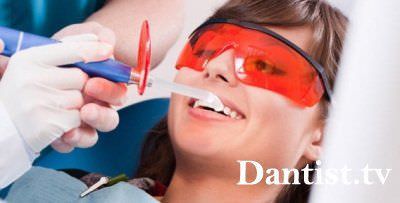

Ultrahang vagy lézeres kezelés

Ez az eljárás elsősorban felszámolásáról fogkő. A választás e két tisztítások függ, hogy pontosan hogyan a készülék rendelkezik egy adott klinikán. Általában ezek mind teljesen ártalmatlan, mivel a technológia olyan, hogy a gép nem is érinti a fogzománcot.

A lézer is működik a víz, de ebben az esetben nem játszik fontos szerepet. Az akció a lézer irányul, hogy a nedvesség, amely található a plakk, miáltal szétesik, és eltávolítjuk a szájüregben útján jet súrolás. Önmagában az intézkedés a lézer antibakteriális hatást, és megakadályozza a további fejlesztése a káros mikroorganizmusok.